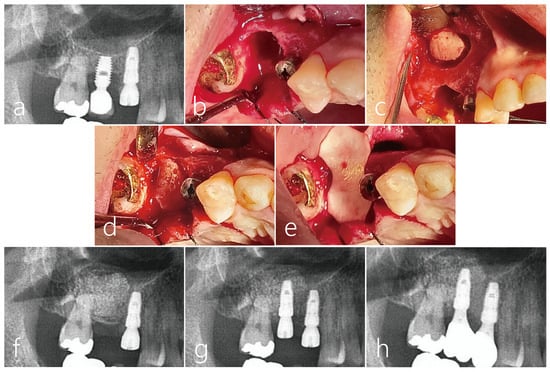

2.1. Case 1

2.2. Case 2

2.3. Case 3

2.4. Case 4